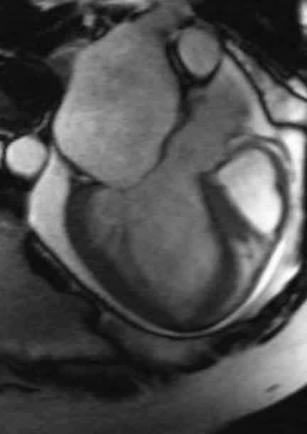

Dr. Ian Paterson

Department of Medicine, Division of Cardiology, University of Alberta

Areas of research:Heart Failure/Transplant

Operating funding provided by: CIHR, AHFMR, Heart and Stroke Foundation